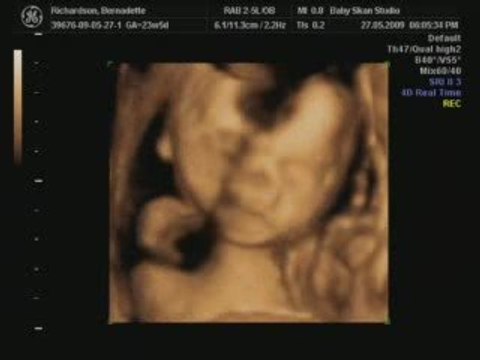

4D Ultrasound Scan Shows Baby In Fetus Dancing

Baby in fetus seen dancing through 4D ultra sound scan. Which became a viral video among netizens. Read detail news at publictv.in Subscribe on YouTube: youtube.com/user/publictvnewskannada?sub_confirmation=1 Follow us on Google+ @ plus.google.com/+publictv Like us @ facebook.com/publictv Follow us on twitter @ twitter.com/PublicTVnews

Ultrasound, Scan, Shows, Baby, Fetus, Dancing